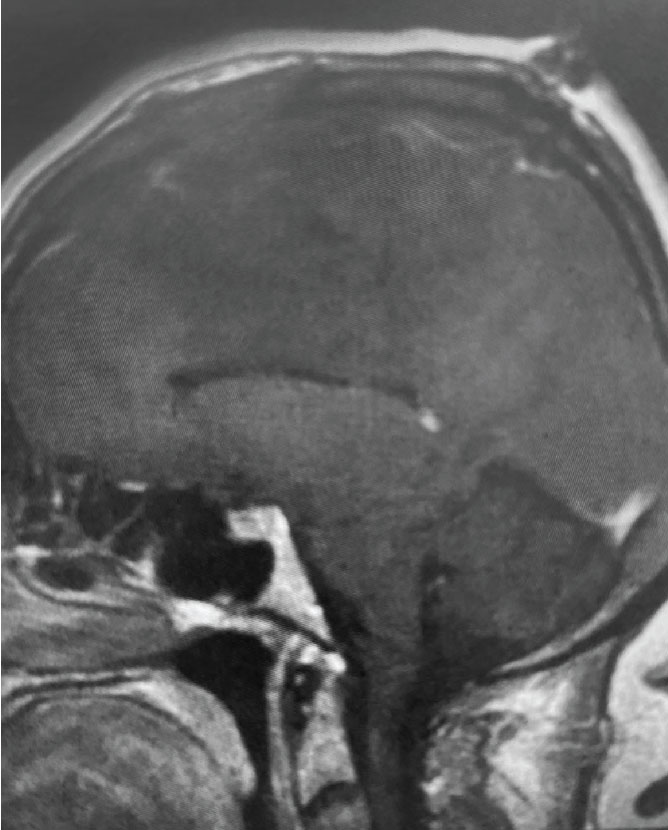

Fig 1. B) Pre-operative, sagittal post-contrast MRI.

This is a 55 year old right-handed woman who was having progressive balance problems. MRI with and without contrast demonstrated a 7 cm partly cystic meningioma involving the left frontal convexity and falx, and encasing the superior sagittal sinus. There was also tumor involvement of part of the convexity skull.